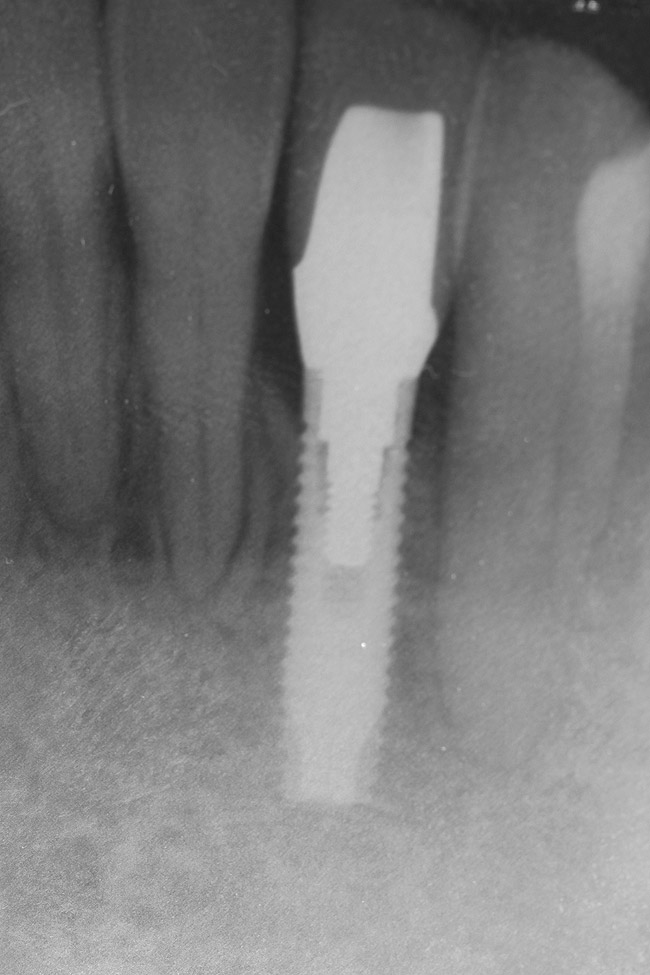

Figure 21  Radiograph of implant in position at the time of surgery of tooth No. 23.

Figure 21